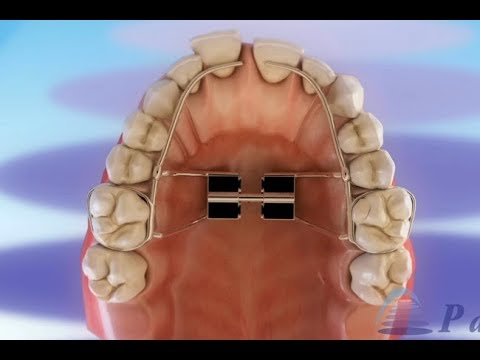

歯科矯正の種類 ©

歯列矯正 – 要素とその役割 ©